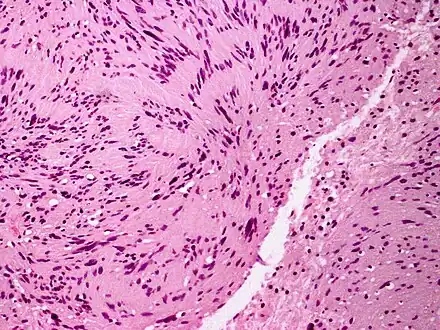

Micrograph of a palisaded encapsulated neuroma

PEN is diagnosed by clinical recognition of the lesion and on subsequent histologic examination. Typically, the lesions are suspected to be schwannomas or neurofibromas clinically with PEN being an incidental finding on histology.[3]

PEN is typically diagnosed in patients between the ages of 40 and 60 years and occurs more frequently in females than males. The diagnosis of PEN may be difficult, even with confirmatory histology, due to its histological similarities with schwannomas and neurofibromas. It is imperative that the correct diagnosis is made the misdiagnosis of a neurofibroma may lead to unnecessary further investigation into associated systemic syndromes such as neurofibromatosis type 1 or multiple endocrine neoplasia syndrome.[3][4]